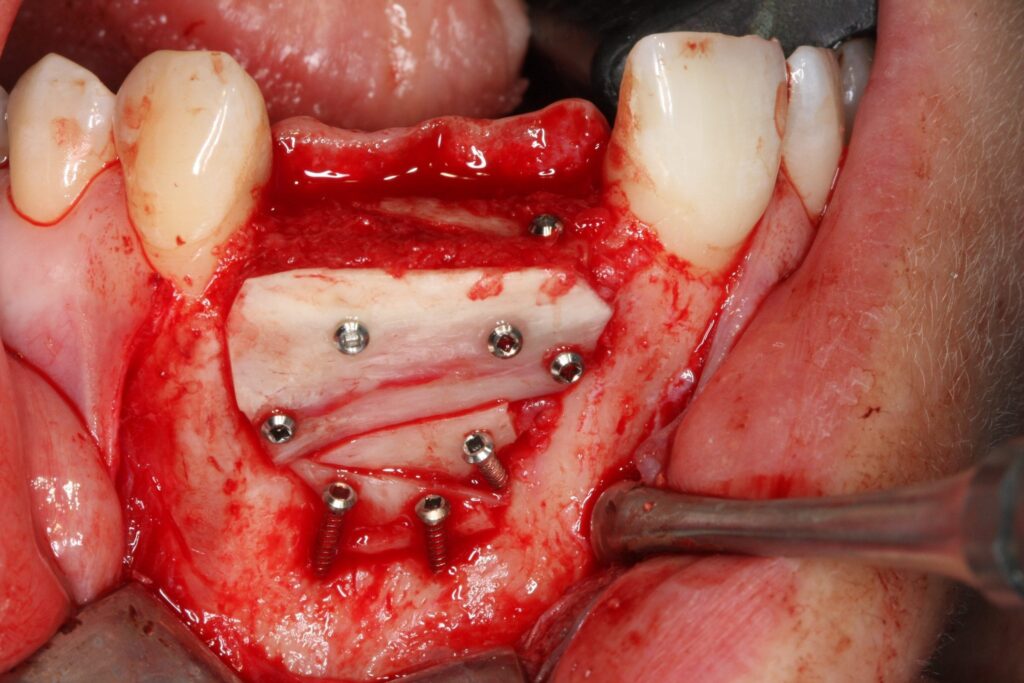

Zunächst einmal mussten die Reste des synthetischen Knochenaufbaumaterials umfangreich entfernt werden. Nur so konnte die Grundlage für einen neuen, nunmehr erfolgreichen, Behandlungsschritt geschaffen werden. Diese Behandlung führte Prof. Dr. Khoury kompetent in unseren Praxisräumen durch. Anschließend konnte mit der Knochenblockaugmentation begonnen werden. Ziel war es, eine stabile und langfristige Grundlage für die Verankerung von Zahnimplantaten zu schaffen.

Ein Zahnimplantat funktioniert als künstliche Zahnwurzel und trägt hochwertigen festsitzenden oder herausnehmbaren Zahnersatz. Diese künstliche Wurzel verbindet sich beim Abheilen fest mit dem umliegenden Knochengewebe. Damit das Implantat später Halt für den Zahnersatz bietet, muss der Knochen ihm genügend Volumen und Stabilität liefern. Deshalb ist bei Vorliegen eines entsprechenden Knochendefizits ein Knochenaufbau mit Eigenknochen aus dem Unterkiefer ein entscheidender Erfolgsfaktor für die spätere Implantation und sollte daher professionell durchgeführt werden.

Implantat getragener Zahnersatz auf aufgebautem Eigenknochen

Nachdem die gewünschte Stabilität des Kieferknochens erreicht wurde, konnte Prof. Dr. Olze mit dem Setzen der Implantate beginnen. Um langfristig für Stabilität und Ästhetik zu sorgen und um einen erneuten Eingriff vermeiden zu können, wählte er in Absprache mit der Patientin hochwertige ANKYLOS®- Implantate und Zahnersatzkomponenten von Dentsply Sirona. Diese Versorgungslösung ermöglicht eine lange Haltbarkeit und mechanische Stabilität. Auch auf ästhetischer Ebene überzeugt diese qualitativ hochwertige Lösung. Hiermit ist sichergestellt, dass die Patientin auch nach Jahrzehnten noch unbeschwert lachen und abbeißen kann. Durch die innovative Knochenaufbaumethode und die nachhaltig konzipierten Implantatkomponenten wird einem späteren Knochenabbau entgegengewirkt und das Gewebe bleibt anhaltend stabil und gesund.